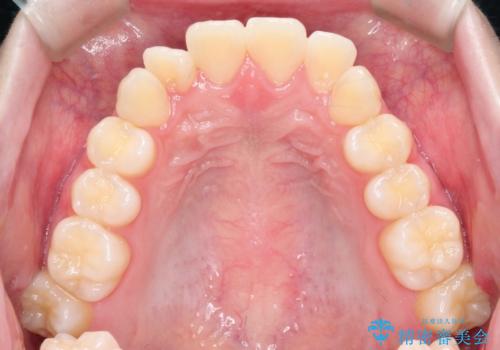

- 前歯のガタガタを主訴に来院されました。

開咬ぎみであったため、しっかりと前歯が噛むように計画を立てて治療をおこないました。

仕上がりも良く、患者様にも満足していただきました。

インビザラインは前歯を噛ませるような開咬の治療も得意としています。